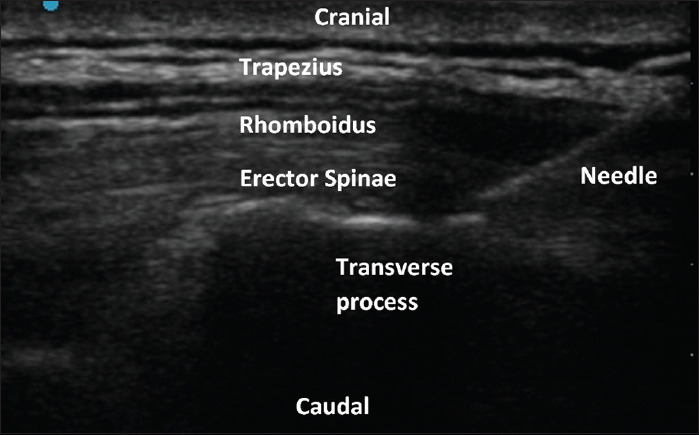

Background and aims: Dexamethasone is used as an adjuvant to prolong the duration of peripheral nerve blocks. This study compares the effectiveness of intravenous (IV) versus perineural dexamethasone as an adjuvant to 0.5% ropivacaine for erector spinae plane block (ESPB) in patients undergoing modified radical mastectomy (MRM).

Material and methods: This prospective, double-blind, randomized study was conducted on 60 American Society of Anesthesiologists (ASA) physical status I/II adult females undergoing MRM under general anesthesia. Patients were divided into three groups: ropivacaine perineural dexamethasone (RPD), ropivacaine IV dexamethasone (RID), and ropivacaine normal saline (RNS). Time to rescue analgesia and morphine consumption over various time points (4, 8, 12, 24, and 48 h) were recorded postoperatively. Pain was assessed using the numeric rating scale (NRS).